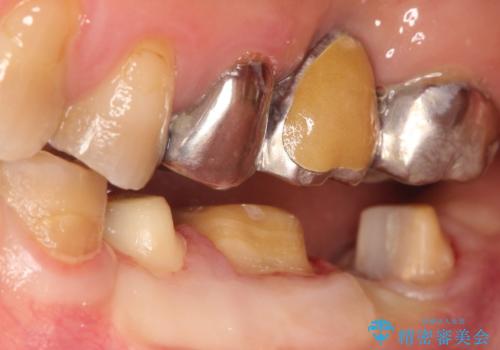

【ヘミセクション】なんとか残したい、割れた奥歯。

- 他院で、抜歯してインプラントだと診断され、セカンドオピニオンで来院されました。

近心根が垂直破折しており保存不可能で抜歯適応だと判断しましたが、できることなら少しでも保存したいとの希望があり、今後のリスクを説明した上で遠心根を保存する意思決定を行いました。

今回の症例は遠心根を保存するメリット・デメリットを患者さんと話し合い、治療を進めております。

条件が少しでもよくなる様に、再生治療および確定外科を行い良好な歯周状態でオールセラミッククラウンを装着しております。